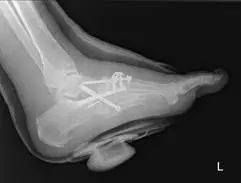

The images below are that of Charcot of the ankle joint. This patient had a wound to the inside of his ankle as he would walk and put pressure on the inside of his ankle because the foot was displaced outward. The patient had a previous ankle fracture that was repaired. However, because of the onset of Charcot neuroarthropathy, the weakening of bones did not allow the structure to hold up after the repaired ankle fracture, causing the breakdown seen in the images. One can see that excessive stress is taken on at the ankle and the screws holding the tibia and fibula together broke.

After over a year of wound care to help the wound on the inside of the ankle heal, the patient was finally stable enough to have surgery to realign the foot underneath the ankle, requiring a fusion of the ankle and subtalar joint with a surgical nail (rod).